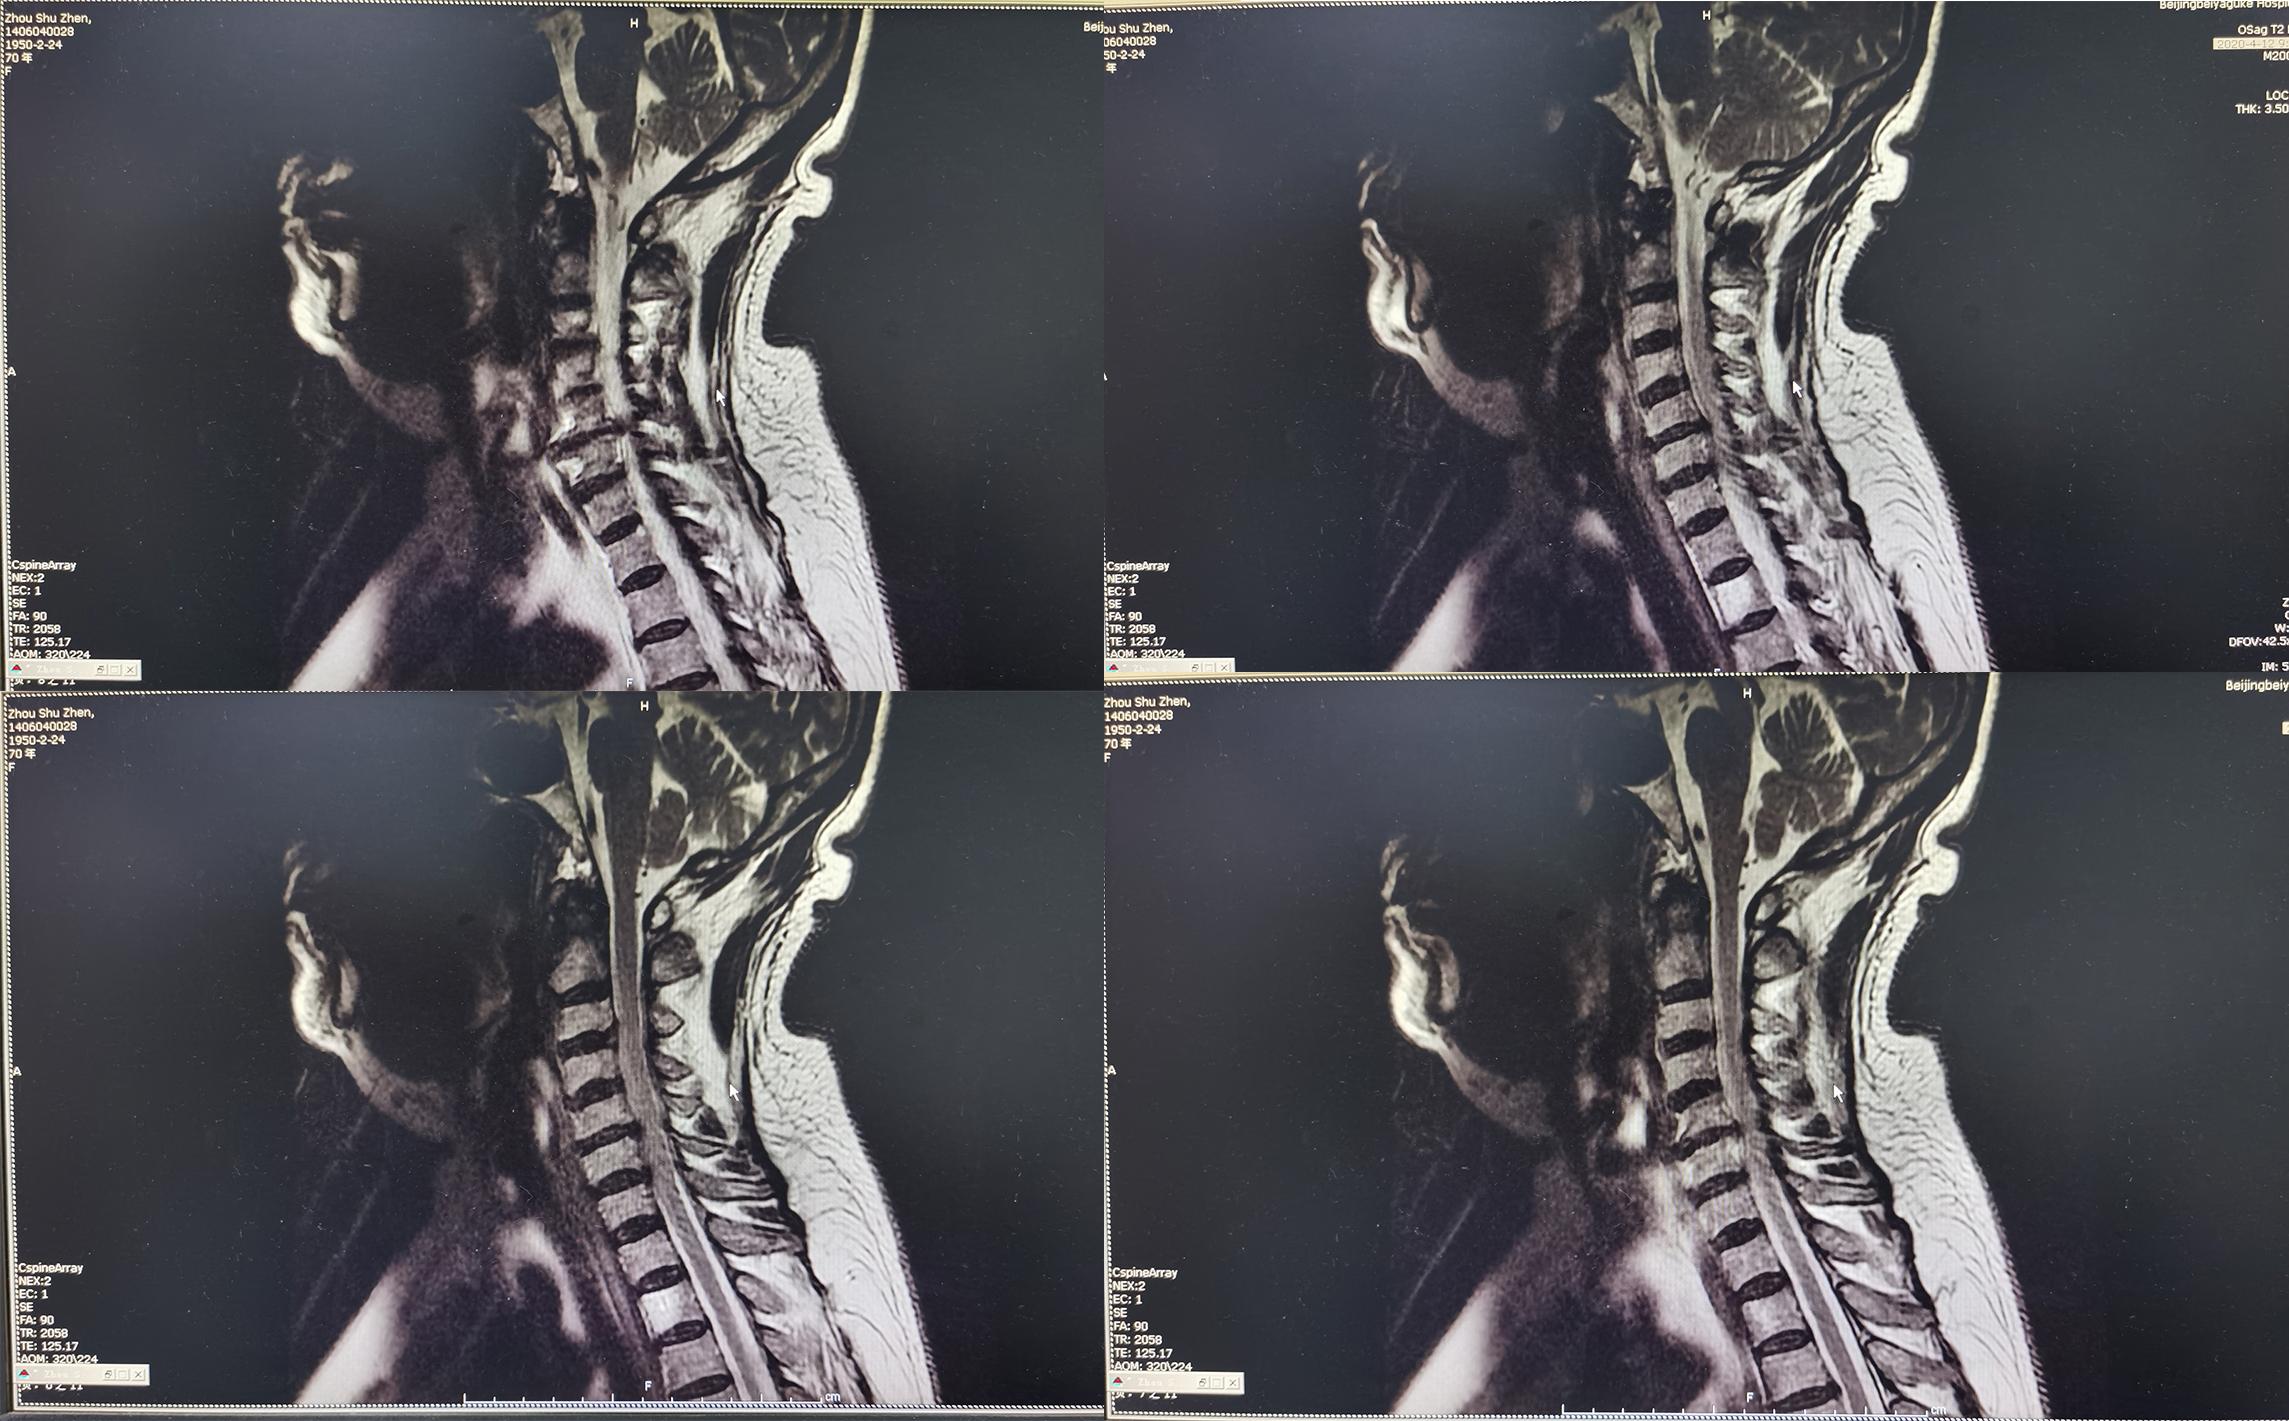

患者因间断性头晕、行走不稳,伴双上肢放射痛,麻木,于2020年4月11日入住北京某三级医院的中医骨伤科,当日查颈椎CT示椎管狭窄性颈椎病(图-1)。

图-1: 2020年4月11日颈椎CT

入院后第二天2020年4月12日查颈椎MR示颈椎病(脊髓型)( 图-2 )。

图-2: 2020年4月12日颈椎MR